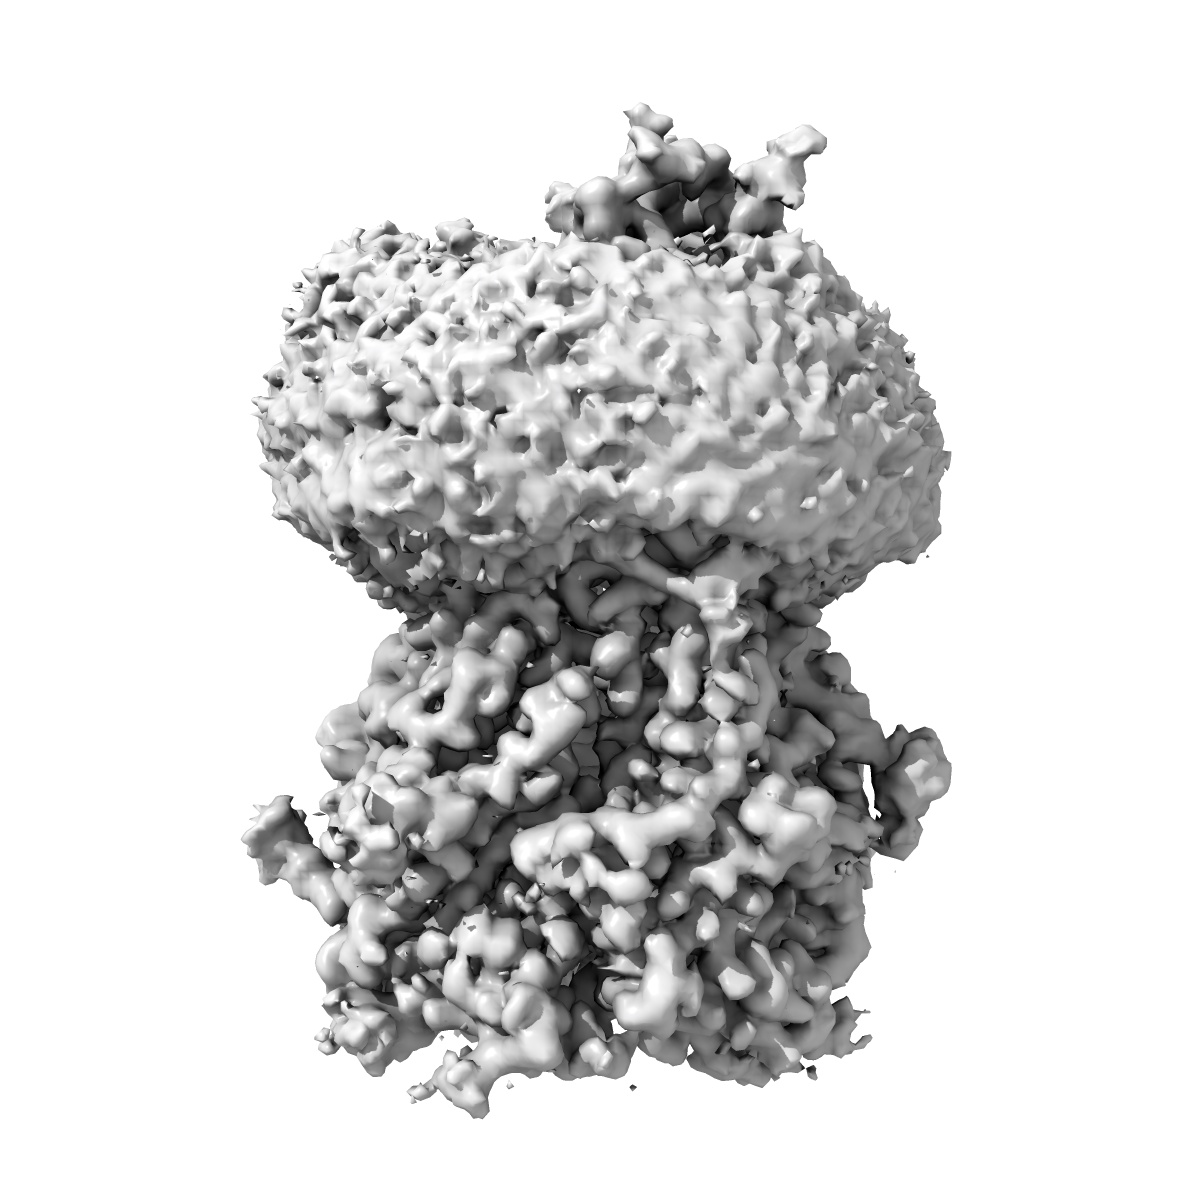

Cryo-EM structure of the full-length alpha1beta3gamma2 GABA(A) receptor in complex with GABA in the short-lived symmetric bound-closed state

Sample: Cryo-EM structure of the full-length alpha1beta3gamma2 GABA(A) receptor in complex with GABA in the short-lived symmetric pre-active state

Cryo-EM structure of the full-length alpha1beta3gamma2 GABA(A) receptor in complex with GABA in the short-lived symmetric pre-active state